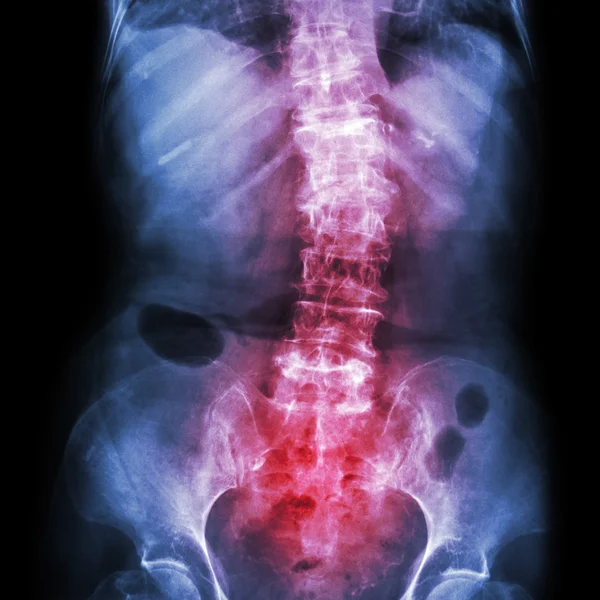

ESPONDILITE ANQUILOSANTE

Cerca de 0,3 a 1,5% da população geral sofre de espondilite anquilosante, um tipo de artrite que afeta, principalmente, as costas e causa inflamação na coluna. A doença pode deixar toda a região rígida e dolorida, incluindo a caixa torácica e pescoço, o que prejudica a qualidade de vida das pessoas. Atualmente, há algumas oções de tratamento disponíveis para melhorar o bem-estar de quem convive com a doença.

A espondilite anquilosante, também conhecida como espondiloartrite, é uma doença inflamatória autoimune que pode causar a fusão de alguns dos ossos da coluna, chamados de vértebras. Esse processo torna a coluna menos flexível e resulta em uma postura curvada. Se as costelas forem afetadas, torna-se difícil respirar profundamente. A enfermidade tem uma maior incidência em:

Raios-x ou ressonância magnética;